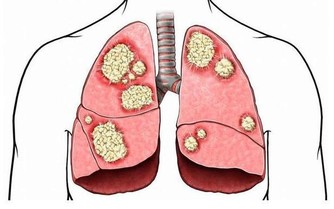

近年來的研究還發現,老人肺炎與各種牙病關係密切。因為口腔內的大量細菌可以被吸入肺部,導致肺炎。